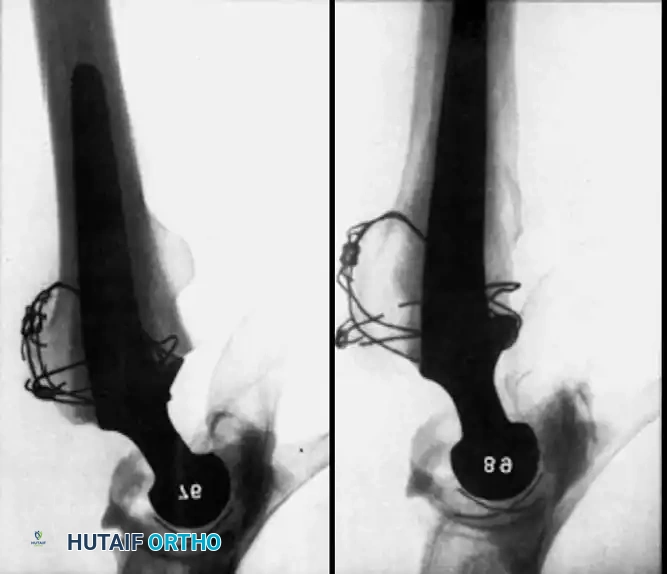

Associated Surgical & Radiographic Imaging